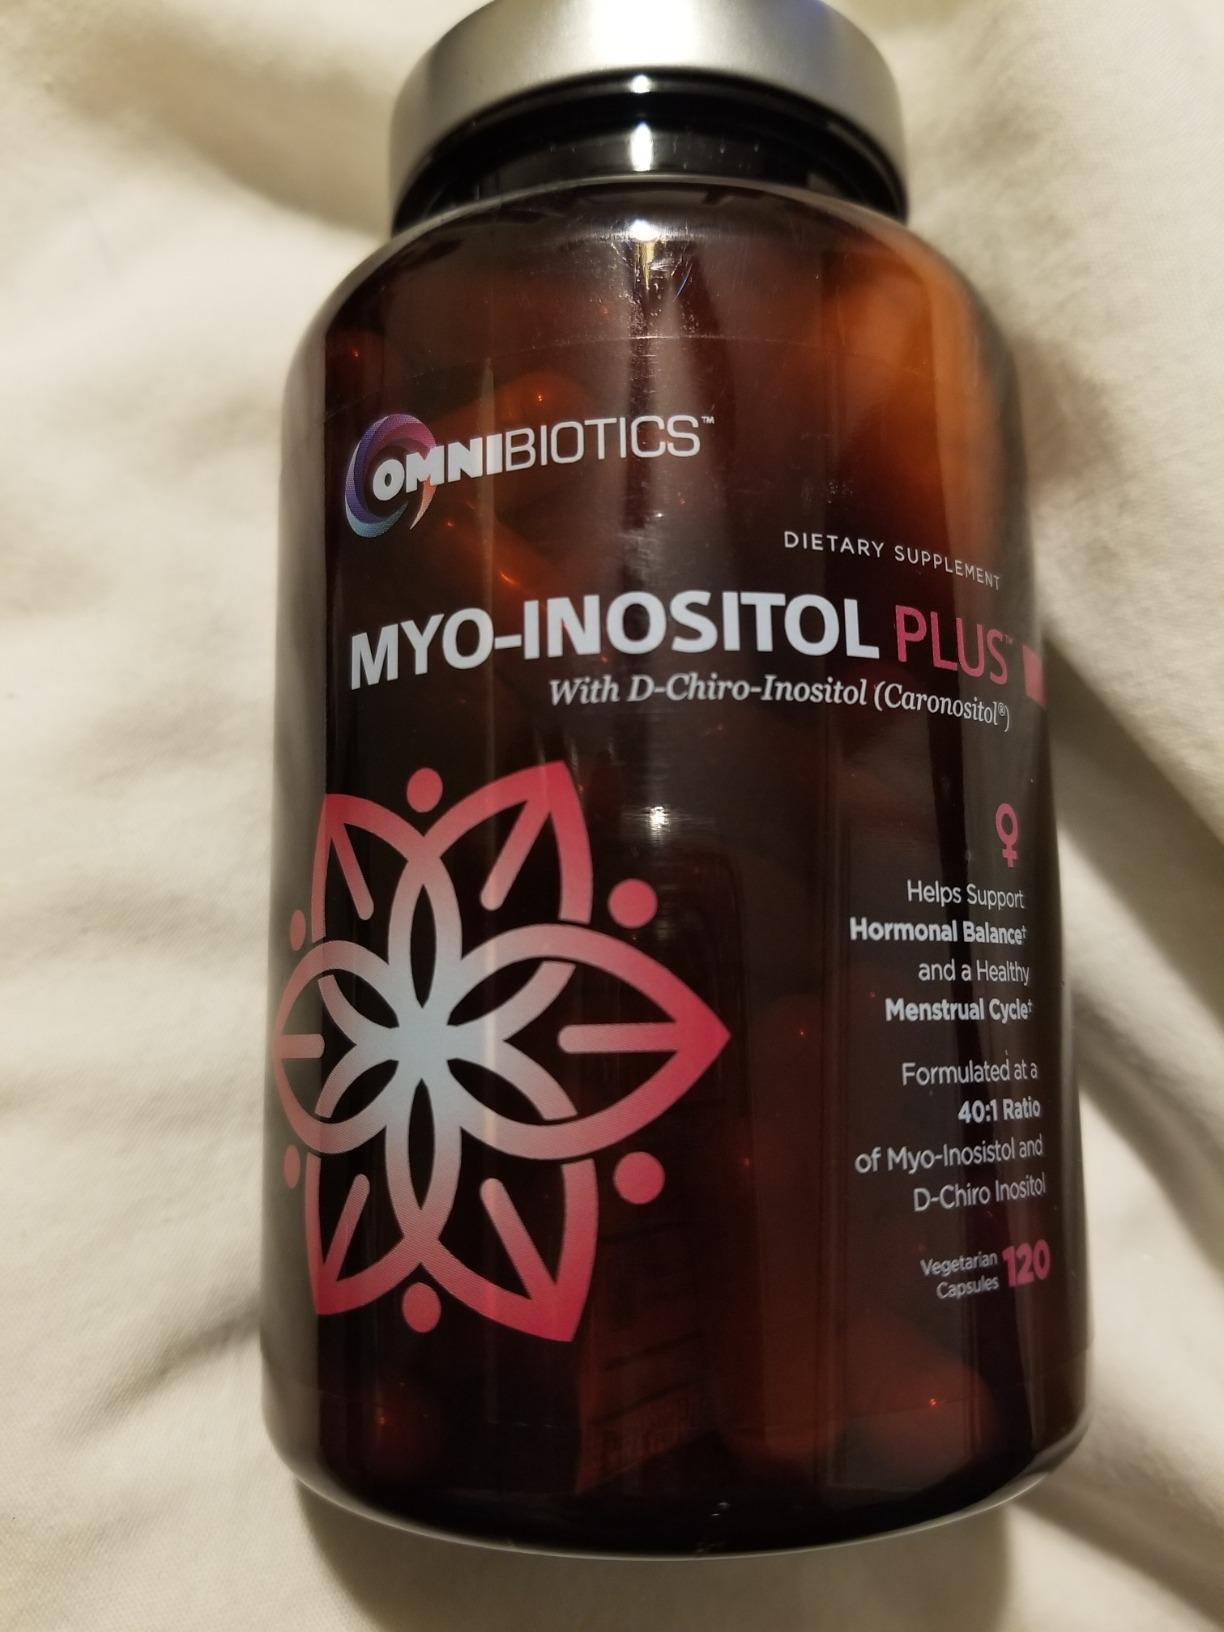

Myo-Inositol Plus & D-Chiro-Inositol | PCOS Supplement | Helps Promote Hormone Balance and Support Ovarian Function | Natural Fertility Supplements (120 Capsules)

Description

OmniBiotics Myo-Inositol Plus with Caronositol features myo-inositol and

d-chiro-inositol at 2,000 mg and 50 mg each respectively, per serving. Myo-

Inositol Plus is a safe and effective myo inositol with d chiro supplement

option. 120 veggie caps 30 day supply These statements have not been

Features:

- HORMONE + FERTILITY + MENSTRUAL CYCLE SUPPORT Specially formulated for women, Myo-inositol Plus contains ingredients that are clinically proven to naturally help support hormone balance, help maintain ovarian function, promote healthy menstrual cycles, and support egg quality. Myo-Inositol Plus is a 100% natural fertility supplement, designed to promote overall reproductive health.

- MOST EFFECTIVE 40:1 RATIO Studies show that the bodys natural 40:1 ratio of Myo-Inositol to D-Chiro-Inositol is the most effective ratio for fertility and reproductive support. Myo-Inositol Plus offers this clinically-proven 40:1 ratio and features Caronositol, a natural D-chiro-inositol (DCI) botanical extract (minimum 95%), purified from carob pods through a solvent-free patented process.

- 100% NATURAL, NON-GMO, NO BINDERS or ADDITIVES Our clinical-strength, Myo-Inositol Plus supplement is 100% free of: gluten, soy, nuts, dairy, sugar, animal by-products, artificial ingredients, chemicals, preservatives and fillers. We also do testing at every stage of the manufacturing process to ensure all ingredients are free of heavy metals. Made in the USA in a NSF-certified, FDA-registered, cGMP facility.

- Brand: OmniBiotics

- Flavor: Unflavored

- Primary Supplement Type: Myo-Inositol

- Unit Count: 120.00 Count

- Item Form: Capsule

- Special Ingredients: Vegetarian, Gluten Free, Vegan

- Diet Type: Vegetarian, Gluten Free, Vegan

- Product Benefits: Hormone Balance

- Manufacturer : OmniBiotics